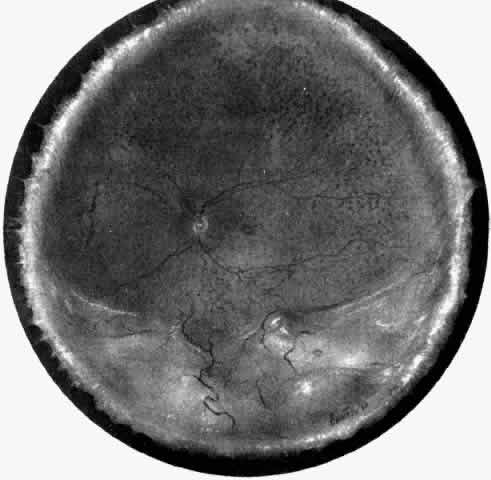

The pathogenesis of uveal effusion syndrome (Fig. 18), also referred to as idiopathic ciliochoroidal effusion, has not been clearly defined, but it is now thought to be primarily due to an abnormality in scleral thickness.92 It is usually unassociated with any other ocular or systemic abnormalities and occurs in the noninflamed eyes of middle-aged men as an insidious, progressive, usually bilateral non-rhegmatogenous retinal detachment with shifting fluid. This detachment can occur before there is any detectable ciliochoroidal elevation. Other findings include flat peripheral ciliochoroidal effusion, scattered retinal exudates, and localized areas of RPE hypertrophy and hyperplasia (“leopard spots”) (see Fig. 1).12,13,69,70,92,94 Evidence of uveal, retinal, or vitreous inflammation is minor or absent (see Fig. 18).

Fig. 18. A nonrhegmatogenous retinal detachment associated with a ciliochoroidal effusion in a 46-year-old man. A ciliary body biopsy, performed because a ring melanoma was suspected, showed a mild lymphocytic infiltrate. Similar changes developed in the fellow eye, and the patient was considered to have uveal effusion syndrome. Exhaustive studies gave no clues to the etiology. The cerebrospinal fluid protein was slightly elevated. During a 10-year period, the patient's vision decreased to count fingers (H & E, × 440). (Courtesy of the Armed Forces Institute of Pathology, Washington, DC)